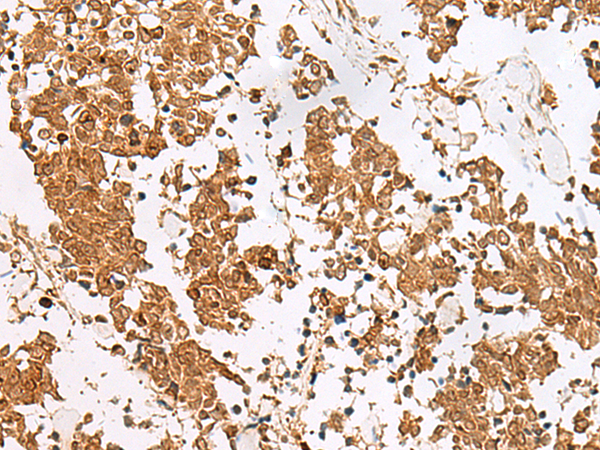

IHC positive control:

Human esophagus cancer and Human tonsil

IHC Recommend dilution:

50-300